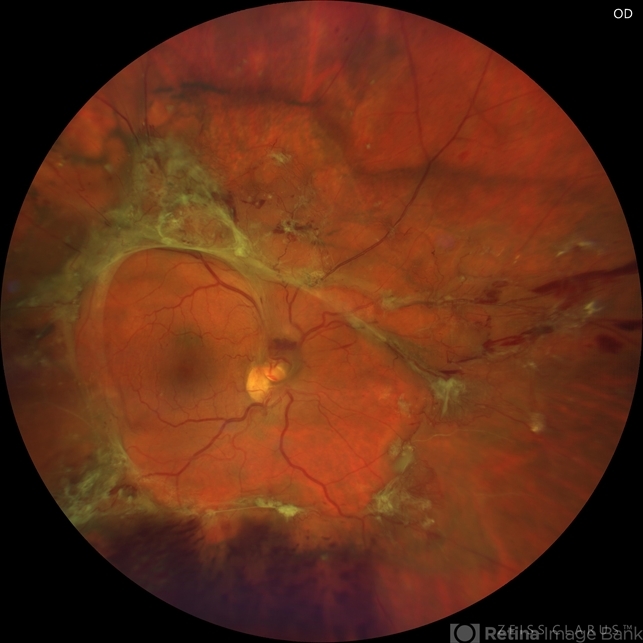

- proliferative diabetic retinopathy (PDR), tractional retinal detachment, hemophthalmos, wolf jaw

- Colour fundus photograph of 44-year-old man with prolipherative diabetic retinopathy and tractional retinal detachment in the shape of wolf jaw.